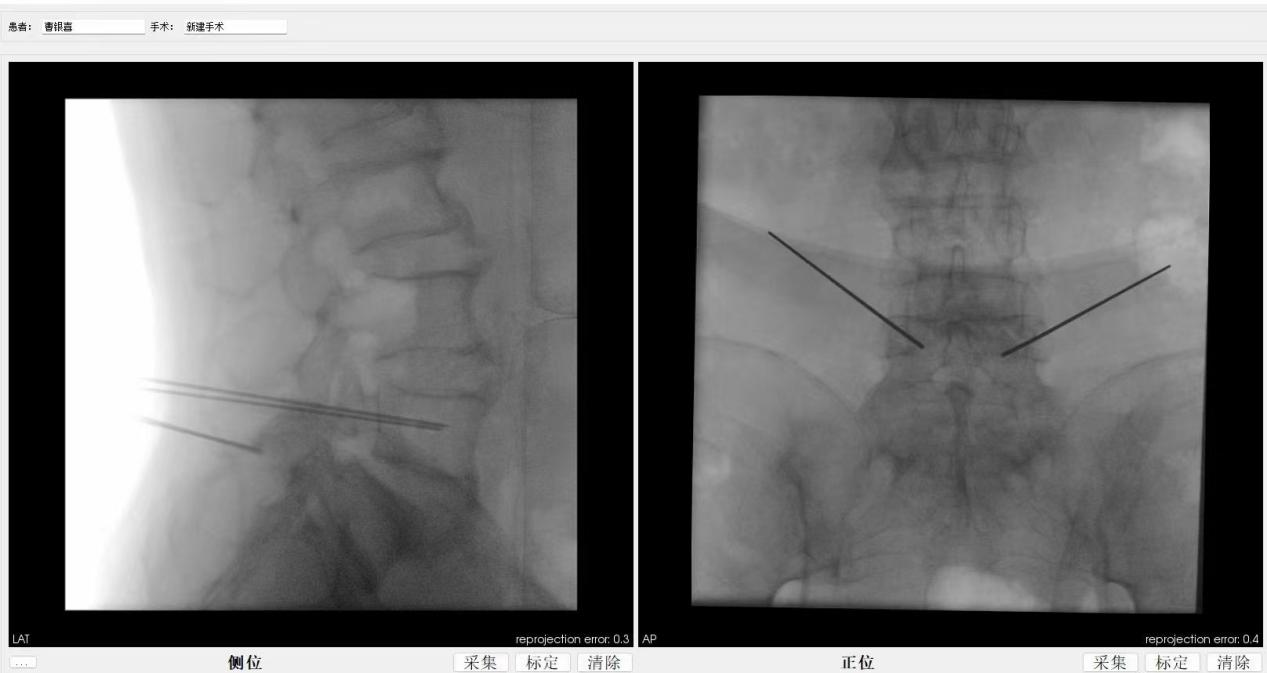

患者术后影像学资料